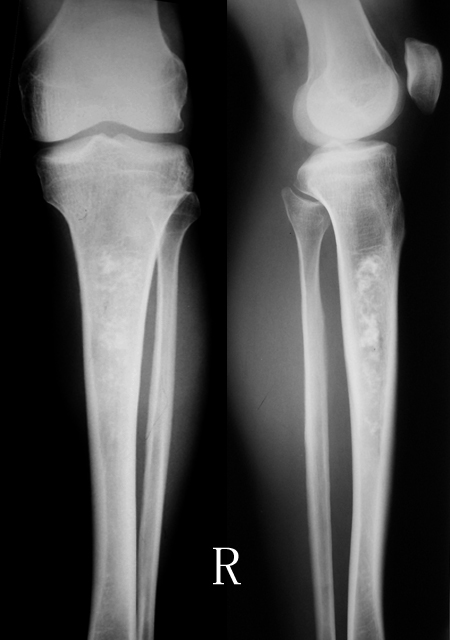

标题: X1101:[原创]右胫骨髓腔内高密度影.考虑啥? [打印本页]

标题: X1101:[原创]右胫骨髓腔内高密度影.考虑啥?

男;53y,外伤一天后摄片发现.无临床症状.

胫骨上段可见斑片状高密度影,密度不均,边界欠清,邻近骨质无破坏,无骨膜反应,周围软组织无肿胀。

多考虑骨梗死可能性大。

胫骨中上段髓腔内可见斑片状钙化,边界较清楚,未见骨膜反应及软组织肿块影。

诊断:胫骨骨梗死。

讨论:骨梗死又称骨髓梗死、脂肪梗死,其病理基础主要是骨髓局部持续性缺血而坏死,逐渐被肉芽组织和纤维组织替代,最终发生钙化和骨化。多发生在股骨下端、胫骨上端和肱骨、股骨上端,呈多发性和对称性改变。引起骨梗死的病因较多,有老龄(多数由于动脉粥样硬化) 、镰状细胞贫血、gaucher′s 病、潜水病、感染、激素、辐射、胰腺炎、血管炎、饮酒及化学治疗等。

x线表现:圆形、椭圆形、片状或不规则形密度增高影,其周边可见若干粗细不等、相互连接或交叉的蜿蜒走行的更高密度影。当骨坏死组织被清除吸收、但尚未新骨形成时,则表现为囊状或分叶状透亮区。sehing 等曾将骨梗死的x线表现分4 型:即带条状、辫状、气泡状、多囊状,典型者表现为地图样钙化。

本例需与骨斑点症相鉴别,骨斑点症类似骨梗死的x线表现,但病灶广泛分布在身体各处,多见于干骺部及骨端,单纯为致密的斑点状阴影。

右胫骨中段髓腔内见斑片状密度增高影,边缘清楚,密度不均,未见骨质破坏,无膨胀变形,周围无软组织肿块,考虑骨梗死。